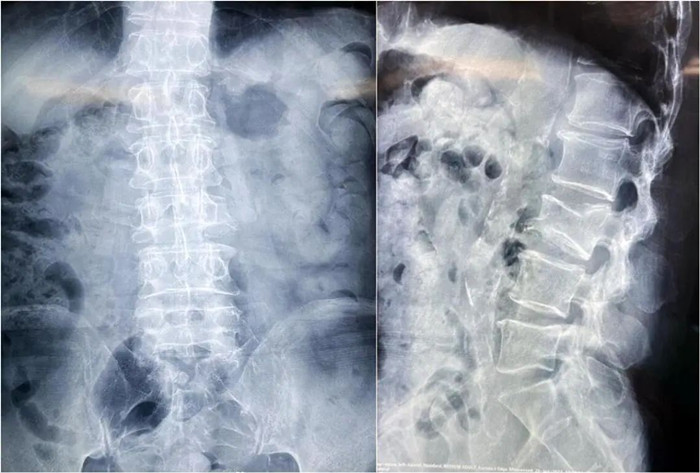

患者情况:腰椎L3压缩性骨折

南京医科大学第二附属医院骨科副主任医师王伯尧带领团队成功完成经皮椎体球囊扩张成形术(PKP)。该患者为腰椎陈旧性压缩性骨折,腰部疼痛难忍,活动受限,生活受到影响。王医生借助普爱医疗大平板C臂机高清的图像及灵活的摆位,快速定位椎弓根位置,确定进针点,使得手术得以更加高效和准确地完成。

患者术前影像